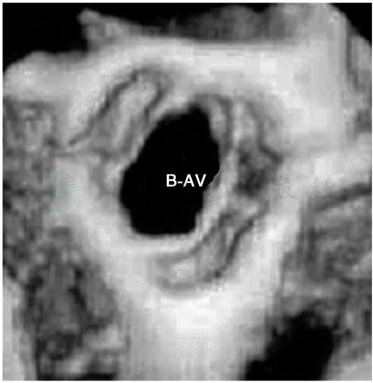

图2二叶式主动脉瓣畸形的三维超声显像

B-AV.二叶式主动脉瓣。

可显示左心室和流出道肥厚。瓣膜狭窄型患者,二维超声心动图显示圆锥形结构的瓣膜在收缩期突入主动脉,动态三维超声心动图可清楚显示其异常结构(图2)。瓣下隔膜型狭窄患者可显示在左心室流出道内有一线状回声,主动脉瓣提早关闭并扑动。多普勒超声心动图可在主动脉内测到收缩期湍流和左心室与主动脉间的压力阶差。